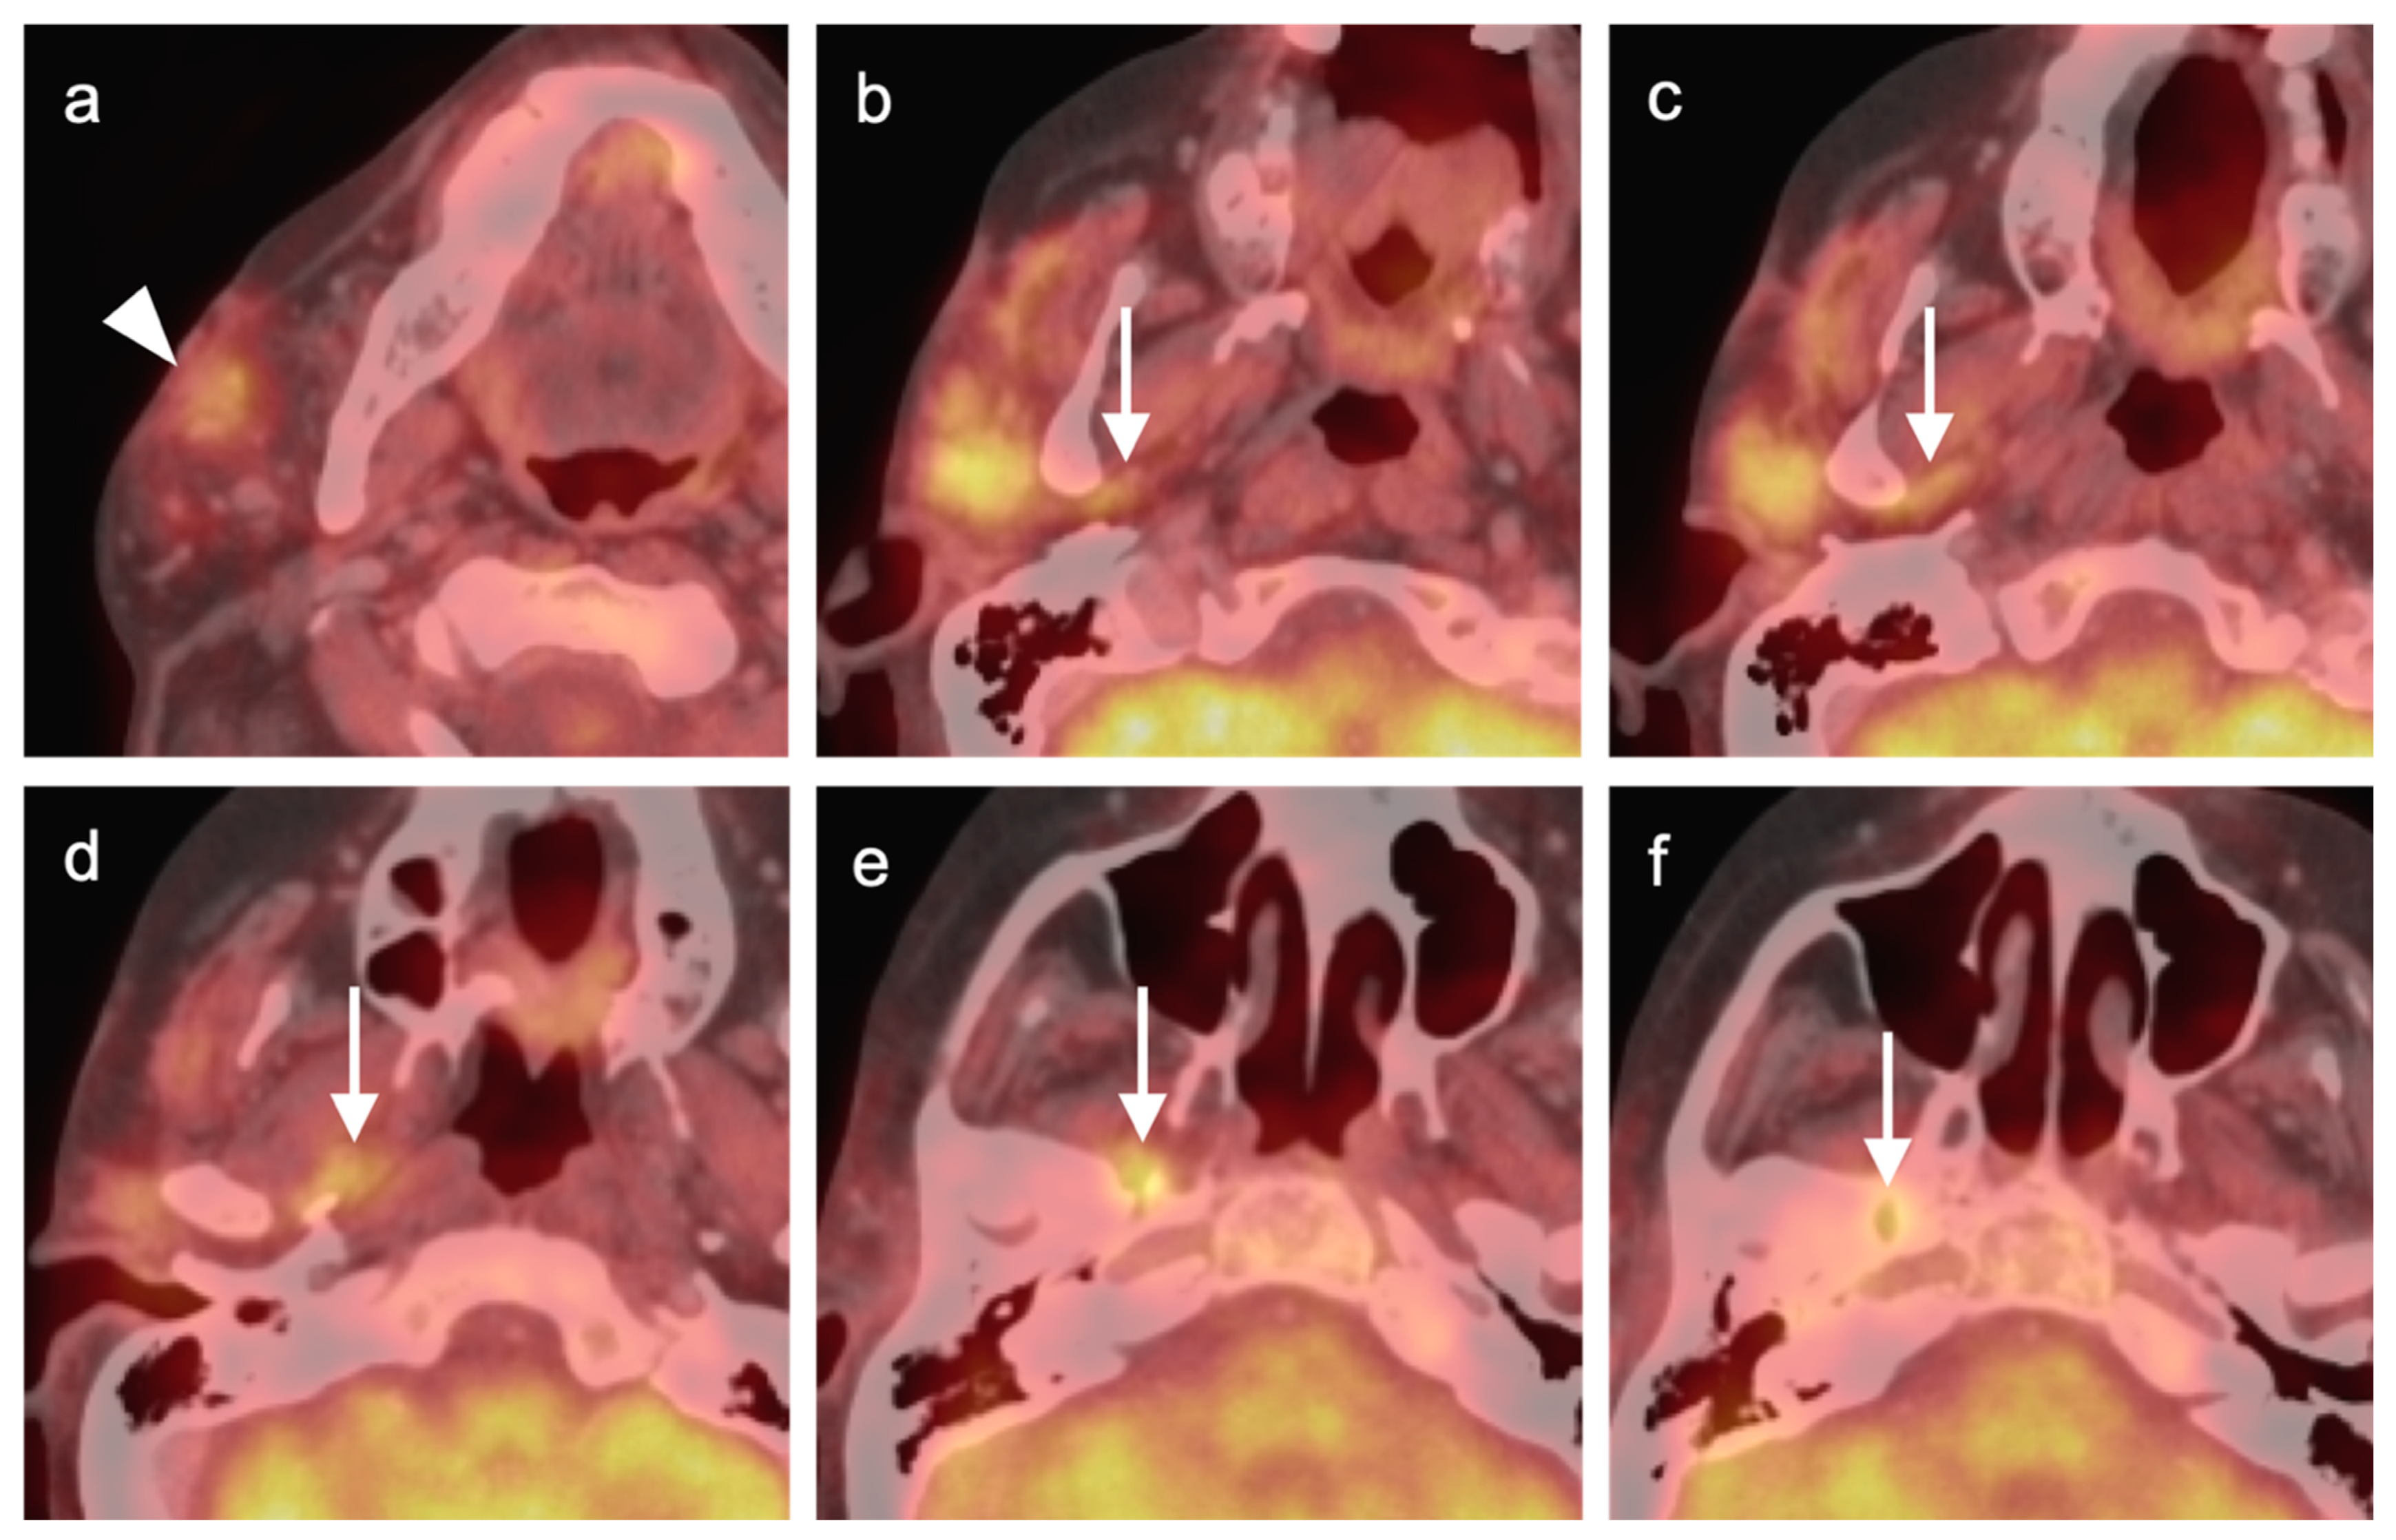

2.4. Sinonasal Tumors

- Sinonasal squamous cell carcinoma

- 2.

- Sinonasal adenocarcinoma

- 3.

- Sinonasal undifferentiated carcinoma

- 4.

- Esthesioneuroblastoma